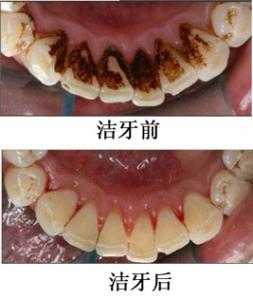

潔牙案例6

潔牙案例6